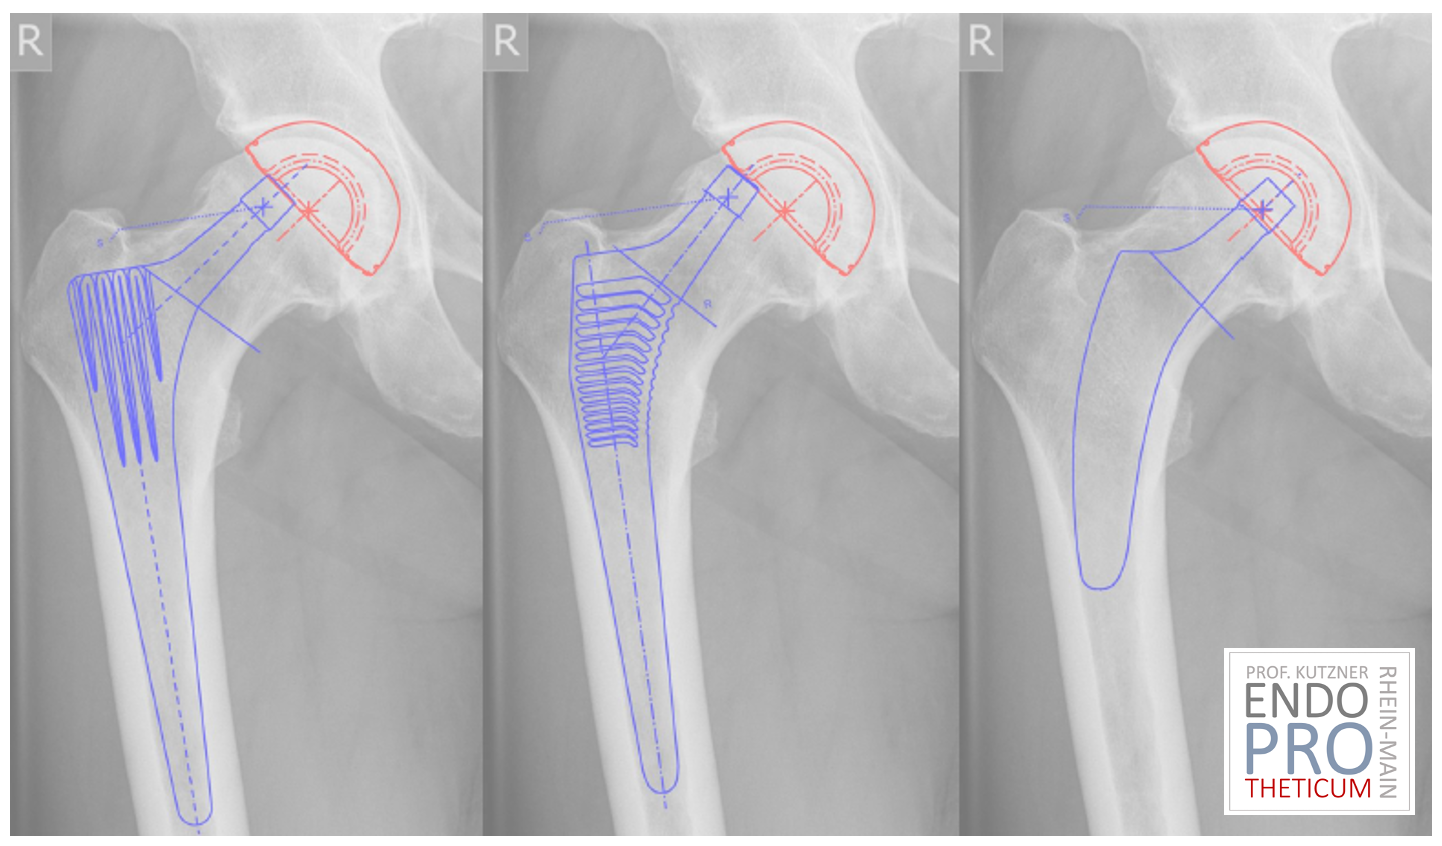

Wenn es um die Behandlung von Hüftproblemen geht, stehen Patienten oft vor der schwierigen Entscheidung zwischen verschiedenen Behandlungsoptionen. In den letzten Jahren sind Kurzschaftprothesen zu einer beliebten Wahl geworden, da sie eine Reihe von Vorteilen gegenüber herkömmlichen Implantaten bieten. In diesem Beitrag werfen wir einen genaueren Blick auf die Vorteile von Kurzschaftprothesen und warum sie für viele Patienten die bessere Option sein könnten.

Im Gegensatz zu herkömmlichen Implantaten erfordern Kurzschaftprothesen oft weniger Knochenentfernung während der Operation. Dies kann dazu beitragen, die Integrität des Oberschenkelknochens zu erhalten und potenzielle Komplikationen wie Knochenverlust oder Femurfrakturen zu reduzieren. Darüber hinaus kann weniger Knochenentfernung die Chancen auf eine spätere Revision der Prothese verbessern, falls dies erforderlich wird.